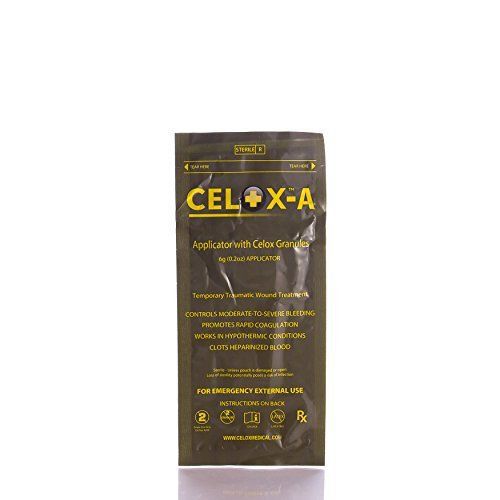

CELOX V12090+ Blood Clotting Granule Applicator and Plunger Set